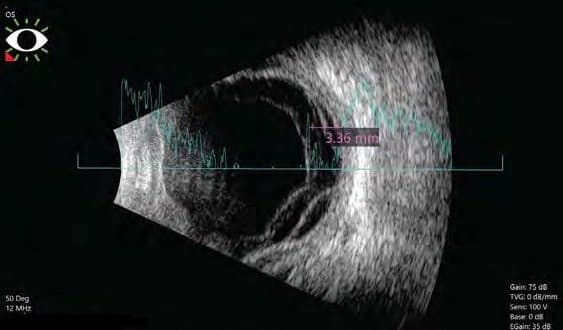

Siêu âm cho mắt sẽ bao gồm siêu âm mắt và siêu âm hốc mắt. Giai đoạn 1 bác sĩ sẽ tiến hành đo kích thước mắt (A-scan), giai đoạn 2 kiểm tra hốc mắt (B-scan) cho phép bác sĩ nhìn thấy rõ không gian bên trong mắt để phát hiện những bất thường. Quy trình thực hiện nhanh chóng chỉ mất 15-30 phút. Sau khi có kết quả siêu âm của 2 giai đoạn kiểm tra trên bác sĩ sẽ đưa ra kết luận cuối cùng.

Đây là bước đầu tiên rất quan trọng để bác sĩ đo đạc nắm được các thông số kích thước mắt. Đồng thời, bước này còn có ý nghĩa trong việc xác định chính xác vị trí cấy ghép thấu kính phục vụ quá trình phẫu thuật đục thủy tinh thể.

Khi thực hiện siêu âm A-Scan, nếu thấy có bất kì vấn đề gì bất thường như có dấu hiệu mắc đục thủy tinh thể hoặc không quan sát rõ phía sau của mắt, bác sĩ sẽ chỉ định siêu âm B-Scan. Đây là bước siêu âm quan trọng giúp quan sát rõ ràng không gian phía sau mắt. Đồng thời, thông qua siêu âm B-Scan, bác sĩ có thể chẩn đoán được mức độ lan rộng của khối u, bong võng mạc hoặc các bệnh lý về mắt khác.